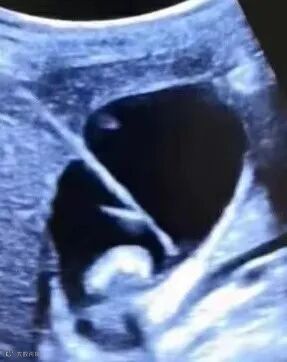

“病家求医,寄以生死;当慎之又慎,精而又精”

镜头中这位正在对患者进行介入治疗的医生,就是我们今天的主人公“强”主任,此时,他正在对一位80岁老人进行了“超声引导下心包穿刺抽液置管术”,这位老人因为大量心包积液,出现了胸闷气短,呼吸困难的症状,随时可能危及生命,要知道介入治疗之所以被称为针尖上的手术,就是因为他对临床医生的要求极高,要求医生下手必须"稳、准、快",不仅对疾病的诊断要准确,穿刺用针更需精准无误,而在没有介入治疗时,心内科医生面对这种情况只能选择盲穿,尤其对于这种没有办法完全配合的老年人来说盲穿风险极大,稍有不慎就会出现严重的后果。如今凭借着他扎实的基本功和精湛的技术,老人的症状在术后得到了明显缓解,患者家属和临床医生悬着的心也终于放下了。

强主任深知介入治疗对于临床医生以及患者的重要性,本着对新技术迫切的追求和对患者高度的责任心,他在西安交通大学第二附属医院对介入超声进行了系统全面的钻研学习,学成归来后,他立刻大力发展超声介入治疗技术。几年来,从无到有,由浅入深,从穿刺胆囊到阻滞细如头发丝般的神经,如今的超声科介入技术已经成熟稳定的开展起来,该技术开展至今,已完成数百例,无一出现重大副作用,强主任大力开展推进的超声介入技术,被认为是西航医院介入治疗史中里程碑式的前进。